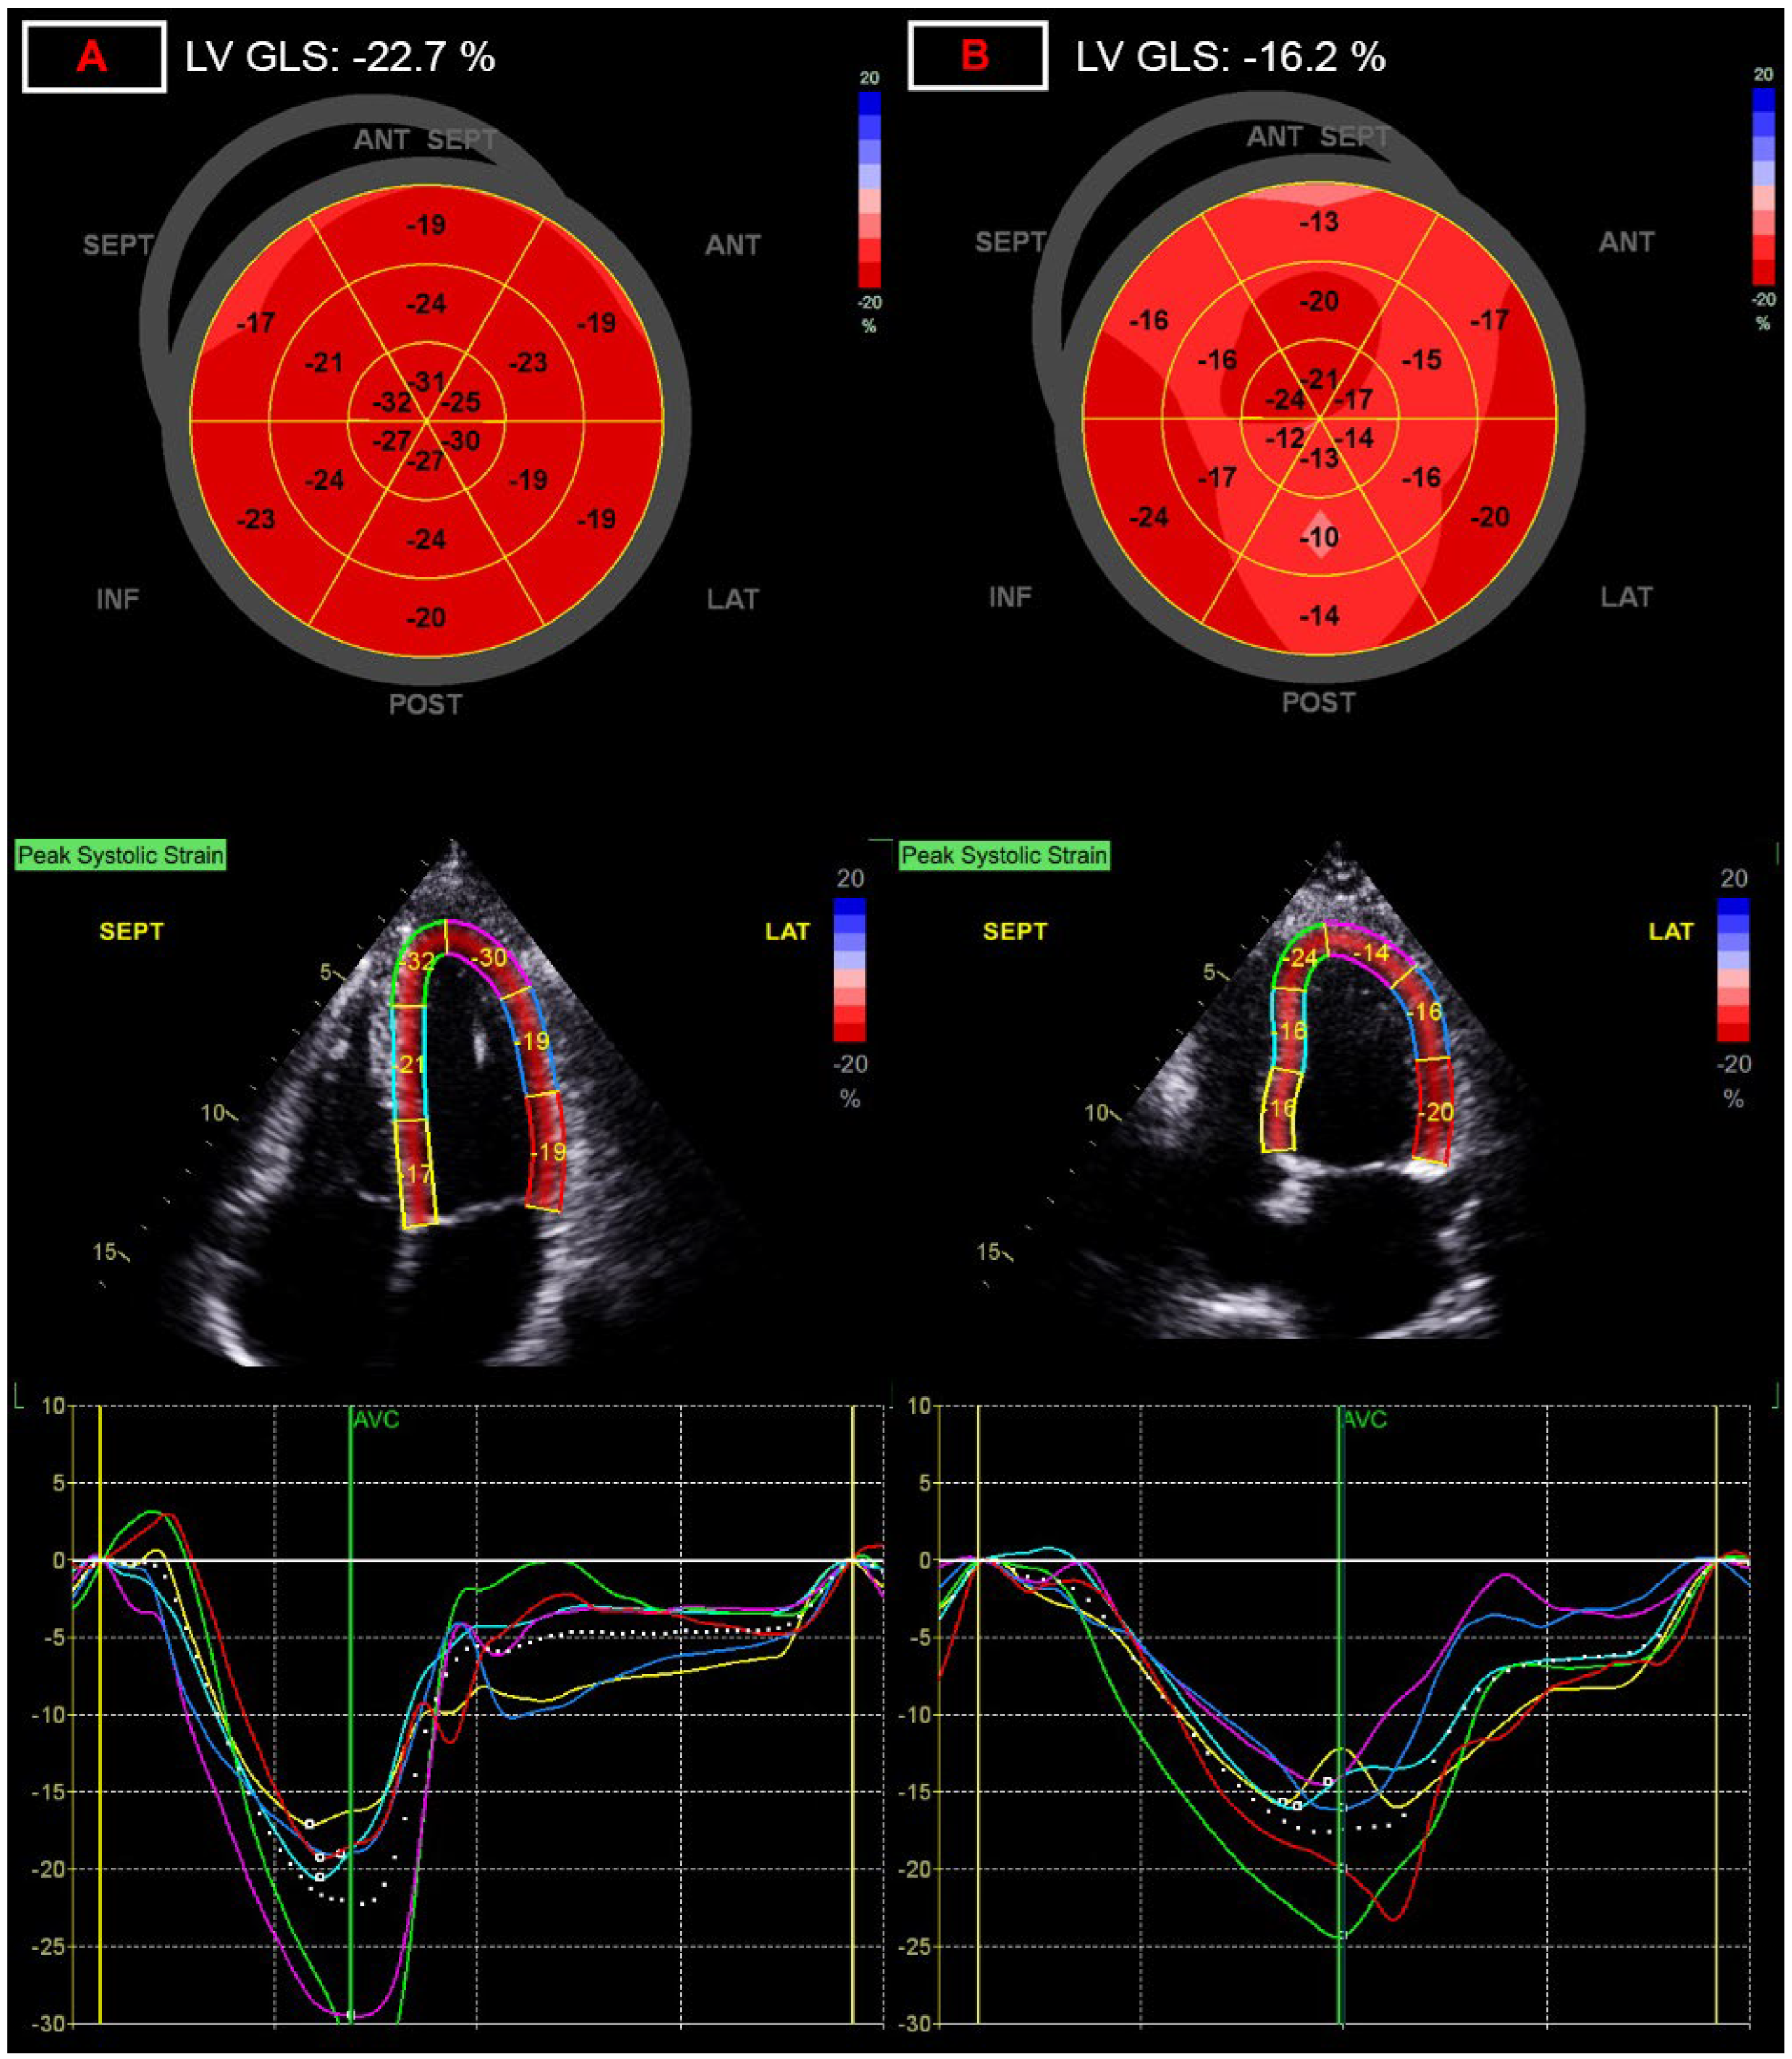

3.2. Functional Parameters of the Left-Side of the Heart

3.3. Myocardial Work Parameters

| LV global longitudinal strain, % | −20.3 (−21.1–−19.0) | −19.1 (−20.4–−17.6) *** | 5.9 |

| LV global work index, Hgmm% | 1975 (1789–2105) | 1829 (1656–2057) ** | 7.4 |

| LV global work efficiency, % | 96 (94–97) | 95 (93–96) * | 1.0 |